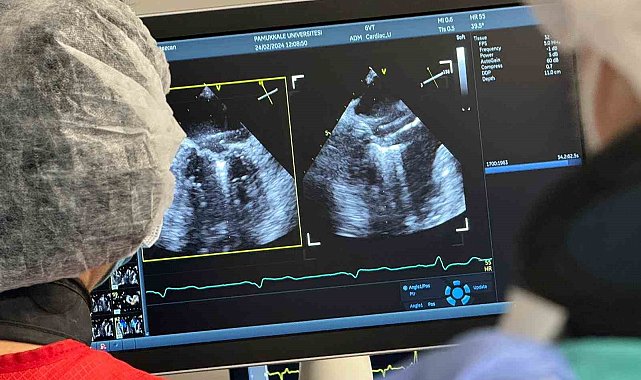

DENİZLİ (İHA) – Pamukkale Üniversitesi (PAÜ) Hastanesi Kardiyoloji Anabilim Dalı, Denizli'de ilk defa yapılan mitraklip işlemini başarıyla gerçekleştirdi.Ameliyatsız mitral kapak yetmezliği tamiri (Mitraklip) işlemi, Denizli'de ilk defa Pamukkale Üniversitesi Hastanesinde Kardiyoloji Ana Bilim Dalı Öğretim Üyeleri Prof. Dr. Doğu Kılıç, Doç. Dr. İpek Büber ve Dr. Öğretim Üyesi Işık Tekin tarafından yapıldı.Mitraklip hakkında bilgiler veren Prof. Dr. Doğu Kılıç, "Mitraklip özellikle kalp yetmezliği hastalarında mitral kapağın kaçağı durumunda uygulanan minimal girişimsel bir tedavi metodudur. Mitraklip metodu tümüyle anjiyo yöntemiyle uygulanmaktadır. Kalp kapak cerrahisi yapılamayacak hastalarda alternatif bir tedavi yöntemidir. Sıklıkla ileri düzeyde mitral yetersizlik olan kalp yetersizliği hastalarına uygulanmaktadır. Romatizmal kalp hastalığı nedeni ile mitral kapak yetmezliği olanlara uygulanmamaktadır. Mitraklip yöntemi, yaklaşık olarak 1 buçuk saat süren bir işlemdir. Bu girişimsel yöntem sonrasında hastalar, kısa sürede günlük aktivitelerine geri dönebilmektedir. Herkese mitraklip yapılması doğru bir yaklaşım değildir. Esas olarak ameliyatı kaldıramayacağı düşünülen, yüksek riskli hastalarda, ağır kalp yetersizliği olan, ileri yaşta olan, böbreklerinde ve diğer organlarında ciddi sorunları bulunan, büyük bir cerrahiyle iyileşme sürecini atlatamayacak düşkün hastalar mitraklip için ideal hastalardır" dedi.Mitraklip sonrası hastanın hayatında yaşanacak olumlu gelişmelere de değinen Kılıç, "İşlem sonrasında hastanın öncelikle kalbe bağlı nefes alamama, nefes düzensizliği yakınmalarında azalma meydana gelir. Hastaların hareket kapasitelerinin artması beklenmektedir. İşlem, kalp çalışırken yapılır. Yani, hastanın kalp-akciğer pompasına bağlanmasına gerek yoktur. Bu nedenle, ameliyatsız bir yöntemdir. Her girişimsel işlemin olduğu gibi Mitraklip işleminin de riskleri vardır. En korkulan komplikasyonları felç, kalp krizi ve ölümdür ve her 100 kişiden 5'inde gelişir" şeklinde konuştu.